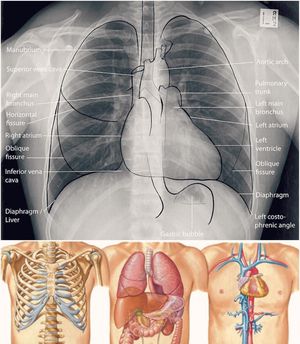

Amazing shot of the chest anatomy labeled on X-Ray

The chest houses organs such as the heart, esophagus, trachea, lungs, and thoracic diaphragm. The heart circulates blood from around the body to the lungs, where the blood receives oxygen from capillaries.